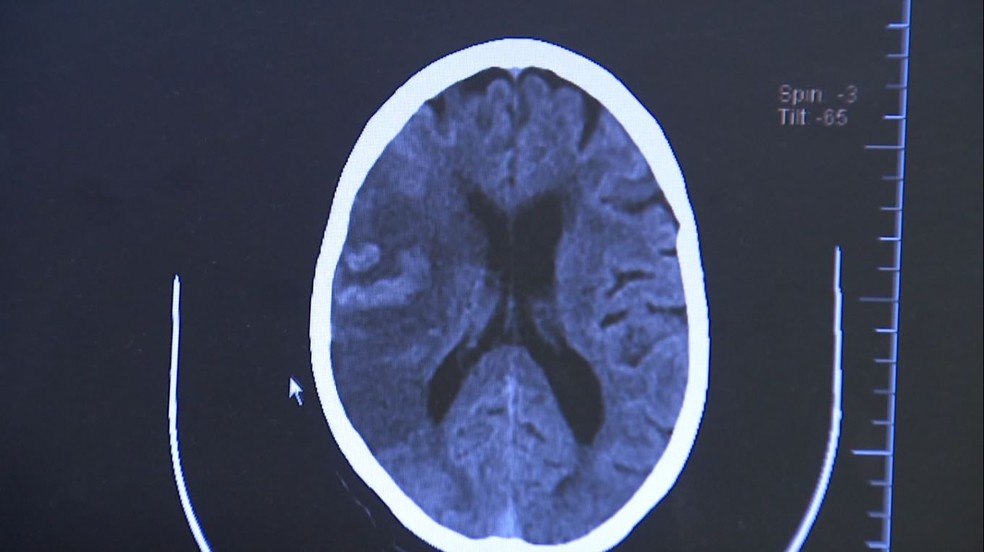

Durante o AVC isquêmico há um bloqueio na artéria, levando à falta de sangue e morte das células cerebrais. Já no hemorrágico, o sangue extravasa por ruptura de um vaso — Foto: Reprodução EPTV

“Durante o AVC isquêmico há um bloqueio na artéria, levando à falta de sangue e morte das células cerebrais. Já no hemorrágico, o sangue extravasa por ruptura de um vaso”, explica o neurocirurgião Feres Chaddad, professor da Universidade Federal de São Paulo (Unifesp) e chefe da neurocirurgia da BP – A Beneficência Portuguesa de São Paulo.

O diagnóstico é feito por tomografia computadorizada ou ressonância magnética do crânio. “Esses exames permitem detectar a área afetada e definir se é um AVC isquêmico ou hemorrágico”, diz Chaddad.